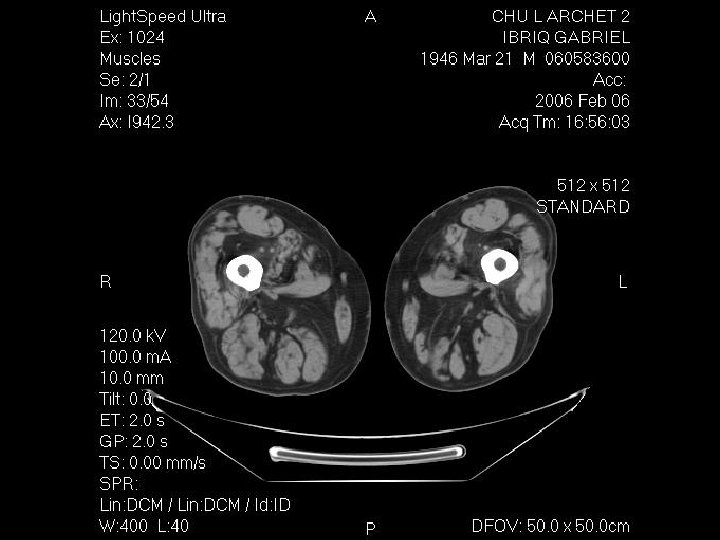

Démarche diagnostic: les examen complementaires Investigation à valeur d’orientation: - Imagerie (scanner, IRM musculaire) Complément indispensable de l’analyse clinique: dépistage atteinte infraclinique, cartographie muscles affectés, préalable à une biopsie IRM si suspicion d’une pathologie inflammatoire; dans les autres cas scanner !!! - Electromyogramme (EMG): Pour évaluer le caractère myogène, recher une myotonie, Stimulation répétitive pour recher une myasthénie etc.